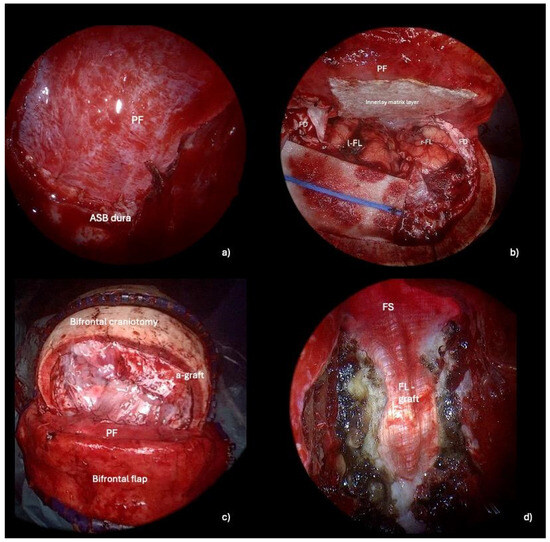

Figure 4. Intraoperative steps of ASB reconstruction method 1: pericranial flap plus autologous fascia lata overlay graft. (a) Endoscope-assisted suturing of the pericranial flap to the dura mater of the planum sphenoidale. (b) Transcranial view of the sutured PF with an underlay (intradural) hemostatic sealing matrix to stabilize the suture between the pericranial flap and the dura mater of the anterior cranial base. (c) Final transcranial view showing the frontal duraplasty made with an autologous pericranium graft and sutured with the autologous dura mater. (d) Final endoscopic endonasal view of the ASB reconstruction: the overlay fascia lata graft is stabilized with absorbable hemostatic material and fibrin glue. Abbreviations. PF: pericranium flap; ASB: anterior skull base; l-FL: left frontal lobe; r-FL: right frontal lobe; FD: frontal dura; a-graft: autologous graft; FS: frontal sinus; FL-graft: fascia lata graft.

2.2.4. Reconstruction Phase

The key to performing an optimal skull base reconstruction is to properly dissect the epidural space over the orbital roof laterally and the ethmoidal roof/planum sphenoidale posteriorly. Specifically, we recommend lightly drilling the lateral and posterior edges of the craniectomy via the endonasal corridor. Simultaneously, under microscopic view, the neurosurgeon dissects the epidural space while protecting the dura of the ASB, assisting the ENT specialist during this delicate phase. By removing the bone, the dura mater of the anterior cranial fossa is exposed, facilitating its suturing to the PF during the transcranial reconstruction. (Figure 3, Video S1). A transcranial approach is employed to repair the anterior skull base defect with a PF secured using button sutures. A hemostatic sealing matrix (e.g., TachoSil®) can be placed underlay (intradural) to stabilize the suture between the PF and the dura mater of the anterior cranial base. Concurrently, endoscope-assisted ASB reconstruction is performed. Additionally, connective tissue, such as temporal fascia or fascia lata, is applied in an overlay fashion to reinforce the reconstruction endonasally. Specifically, the fascia lata is carefully positioned as an overlay graft, covering the defect area to reinforce the primary reconstruction performed with the PF. (Figure 4). The surgical procedure is shown in Video S1.

When the nasal septum is unaffected by the tumor or in cases of post-traumatic defects, the septal branches of the sphenopalatine artery (SPA) can be preserved, allowing for the harvest of an NSF. This flap can then be used as a third layer in ASB reconstruction, providing robust vascularized tissue that enhances the structural integrity of the repair and promotes improved healing. Nasal packing is then applied and removed after 48 h. The bone flap is reattached using titanium plates and screws, while the skin flap is secured with button sutures.